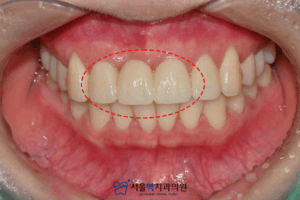

환자분의 여러 가지 상황을 고려하여

제작한 보철물을 부착한 모습입니다. : )

전과 다르게 색상과

모양 등을 고려하여 정밀하게 제작하였으며,

전과 다르게 심미적인 부분이

많이 보완된 것을 확인할 수 있었습니다.

환자분께서도 자연스럽다며

긍정적인 반응을 보이셨답니다.